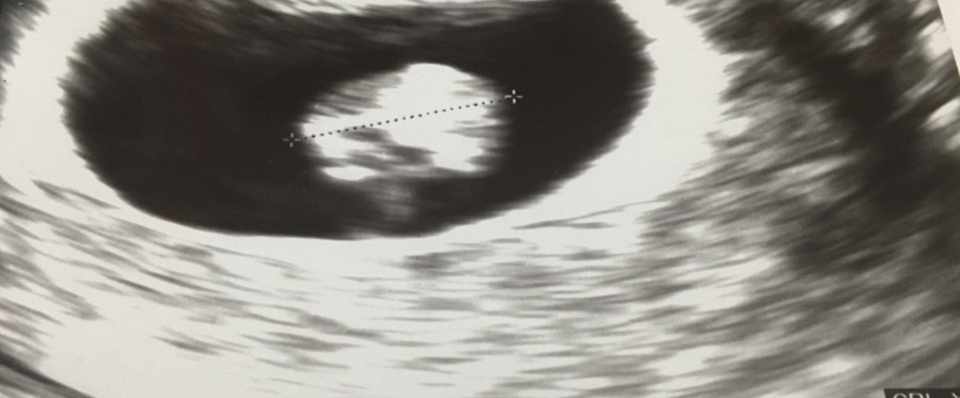

妊娠7週 写真

妊娠7週 写真. 青枠が妊娠何週目かを表す部分、この写真は7wやから7週目を指しとるわけや。 黄色枠で囲った部分が 赤ちゃんの大きさ やで! 10.8mm 、ようは1センチくらいや。まだまだ小さいわ。 妊娠9週目のエコー写真(胎児の大きさや状態). 妊娠7ヶ月(27週)のお腹 妊娠7ヶ月に入り、さらにお腹のカーブが大きくなりました。 この写真は7ヶ月に入ってすぐの写真ですが、月の後半から一気に妊婦感が増してきます。 この頃から、ひどい腰痛に悩まされるようになりました。 妊娠8ヶ月(31週)の. 妊娠8週の赤ちゃんの特徴 妊娠3ヶ月の第1週である「妊娠8週」は、妊娠初期も半ばを過ぎたころにあたります。 このころの赤ちゃんはどのように育っているのかをみていきましょう。 赤ちゃんはどのくらいに成長しているの?.